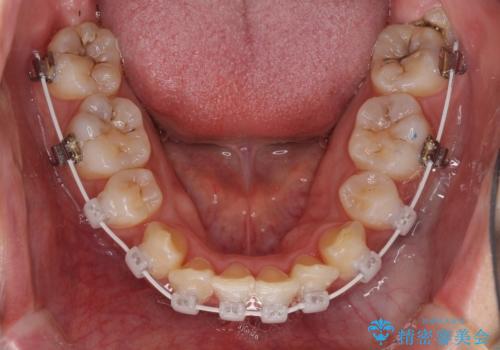

インビザラインが続けられない ワイヤー矯正での抜歯矯正 その1

- インビザライン・審美装置

- 八重歯やデコボコをインビザラインで治療したいとのことで来院された患者様です。

インビザライン単体で治療を行うには叢生が強いと判断されたため、事前にワイヤー装置で抜歯矯正を行い、ある程度改善してからインビザラインにて仕上げていくこととしました。